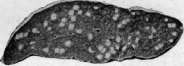

гематогенной генерализацией в результате проникания туб. бацил в ток крови непосредственно или через посредство лимфы (см. Туберкулез). В легких гематогенное поражение проявляется разно. При обшем милиарном Т. в обоих легких наблюдается высыпь массы милиарных туберкулов [см. отд. табл. (ст. 119—120), рис. 3]; в этих случаях ткань легких представляется полнокровной и на таком фоне видны бугорки в зависимости от возраста и типа их или мелкие, серые, полупрозрачные или желтые, с неровными контурами, часто более крупные. Нередко можно, согласно указанию Рибберта (1902), заметить, что у взрослых в верхних районах легких бугорки несколько более крупны, чем в нижних, что объясняют более энергичным ростом туберкулов именно в верхних отделах легких. Если проникание туб. бацил произошло в ветвь легочной артерии, то мидиариза-ция захватывает лишь соответствующую часть легочной территории. Микроскоп, исследование при милиаризации в легких может открыть разный тип бугорков: иногда это типичные продуктивные эпителиоидные бугорки, имеющие своим источником развития альвеолярные перегородки; бугорки растут, сдавливая и уничтожая альвеолы и оставаясь долго продуктивными бугорками; в других случаях к бугорку, начавшему развиваться в альвеолярной перегородке, быстро присоединяется эксудация в альвеолы; наконец бывает так, что бугорок как бы сразу возникает в виде милиарной пневмонии, захватывающей 2—4 соседних альвеолы (милиарный альвеолит), и таким образом обнаруживает экеудативный характер. Гюбшман и Шлейсинг выдвигают ту точку зрения, что всякий бугорок в легких начинается в виде милиарной пневмонии и уже потом окружается продуктивной зоной. Эта точка зрения вызвала категорические возражения крупнейших патологов (Герксгеймер, Ашоф, Штернберг и др.); кроме того Гретман (Grethmann, 1928) установил, что гематогенные милиарные бугорки в легких как правило развиваются в виде продуктивных бугорков из стенок мелких сосудов; эксудация в альвеолы есть явление последовательное, частое, но не обязательное. Гематогенное метастазирование в легкие может еще происходить в виде появления в легких одного или нескольких туб. очагов; по своему существу такая форма есть частное проявление органного T.j возникающего в порядке поздней генерализации первичного Т. (см. Туберкулез). Судьба и выражение таких отдельных гематогенных фокусов в легких бывает разной (см. ниже). Попытка Симона (Simon) объяснить все верхушечные рубцы, встречаемые в легких взрослых, гематогенным метастазированием, происходящим в детстве, у патологов не имела успеха; такое гематогенное метастазирование в верхушку легкого в детском возрасте встречается редко и на детских трупах мы не встречаем ничего похожего на начало образования этих очагов; верхушечные рубцы легких наблюдаются почти только у взрослых, и частота их возрастает с возрастом. Первичный Т. приводит к смерти детей или в связи с значительным распространением туб. процесса в легких или в связи с генерализацией, особенно в виде общего милиарного Т. и туб. менингита, У взрослых первичный Т. легких бывает очень редко; чаще всего это касается тех народностей, к-рые в детском возрасте не соприкасаются с туб. вирусом (см. Туберкулез).—В торичный Т. легких представляет собой то, что принято выделять в качестве легочной чахотки взрослых; по существу это—вспышка туб. процесса, или реинфект в легком у индивидуума, к-рый уже перенес первичную инфекцию и является относительно иммунным к туб. вирусу. Главной особенностью вторичного Т., или реинфекта является то, что процесс протекает б. или м. изолированно в легком, не обнаруживая склонности к лимфогенным и гематогенным метастазам. Если пат. анатомия легочной чахотки взрослых уже давно разработана достаточно хорошо и представляется б. или м. ясной, то этого нельзя сказать относительно патогенеза начальных изменений. В прежнее время, когда еще не делалось различий между Т. детского возраста и Т. взрослых, когда еще не было ничего известно по поводу первичного и вторичного Т., аллергии и пр., казались совершенно очевидными два обстоятельства: 1) легочная чахотка взрослых есть следствие аэрогенной инфекции легкого туб. палочкой; 2) легочная чахотка взрослых всегда начинается в области верхушки легкого. Изучение строения начальных фокусов Т., обнаруживаемых в верхушках, показало (Birch-Hirschfeld,1899; Schmorl,1901), что в них дело идет о туб. поражении стенки апикального бронха и развитии в таком месте бронхита с перибронхитом. Абрикосов (1904) при своих исследованиях начальных туб. очагов верхушек пришел к несколько иному заключению; он нашел, что поражение обычно начинается ниже, именно в районе 2-го дорсального субапикального бронха верхней доли и что фокус имеет бронхопневмонический характер. Абрикосов высказался за то, что процесс начинается со стенки внутридольковой бронхиолы и быстро принимает бронхопневмонический характер. Эти исследования подвели как бы фактический фундамент под теорию аэрогенного происхождения легочной чахотки; отчасти в связи с этим взгляды Ауфрехта (Aufrecht, 1900) и Рибберта (1901) о гематогенном происхождении легочного Т. взрослых не имели никакого успеха. После того как выдвинулось положение о патогенетическом отличии Т. детского возраста и Т. взрослых и сущность этого отличия была разъяснена в учении Ранке (см. Туберкулез), стало очевидным, что так просто смотреть на генез легочной чахотки взрослых, как это делалось раньше, нельзя. Раз оказалось, что легочная чахотка взрослых есть Т. организма, уже перенесшего туб. инфекцию, то естественно стали говорить, что в основе Т. взрослых лежит вторая инфекция, или реинфекция туб. вирусом. Механизм этой реинфекции понимался различно. По учению Ранке, реинфекция представляет собой не что иное, как обострение-изменений, относящихся к первичному Т. детского возраста (эндогенная реинфекция); т. о. Т. взрослых есть продолжение Т., идущего с детского возраста, но обостряющегося у взрослого, находящегося в состоянии относительного иммунитета к туб. вирусу. В противоположность этому Ашоф и др. стали настаивать на том, что легочная чахотка взрослых в громадном большинстве случаев есть следствие новой аэрогенной инфекции легкого, т. е.— экзогенная реинфекция или суперинфекция организма, уже перенесшего первичную.инфекцию. В последние годы очень многие фтизиатры склонились к мнению, что легочная ча- хотка взрослых есть следствие эндогенной реин-фекции по гематогенному пути. Источником такого гематогенного метастазирования в легкое являются или очаги первичного комплекса в легком и в лимф, железе средостения или туб. фокус в каком-нибудь органе, развившийся в порядке органного туберкулеза. Другой спорный пункт, выявившийся в последние годы, касается места начала легочной чахотки взрослых. До 1925 г. учение о том, что легочная чахотка начинается с самой верхушки легкого к что встречающиеся в верхушках рубцы с петрификатами и без них являются как раз выражением такого начала, не получившего в дальнейшем развития (зажившие очаги реинфекта), казалось совершенно незыблемым. В 1925 г. Асман (Assmann), в 1926 г. Редекер (Redeker), а в ближайшее время Ульрици, Ромберг, Лидтин (Romberg, Lydtin) и мн. др. на основании клинических и рентгенологических данных стали настаивать на том, что вышеуказанные верхушечные очаги никакого отношения к началу легочной чахотки не имеют, что легочная чахотка начинается не в верхушке, а в той области верхней доли, к-рая проецируется непосредственно ниже ключицы; как раз здесь начинается процесс в виде очага пневмонии, что и было обозначено как и н -ф р а к л а в и к у л я р н ы й (подключичный) инфил ьтрат или ранний ту б. инфильтрат (нем. Fruhinfiltrat). С такой точкой зрения не могли согласиться патологоанатомы (Ашоф, Graff, Гюбшман, Loeschke и др.), которые утверждали, что инфракдавикудярный инфильтрат не есть анат. начало легочной чахотки, а лишь клинико-рентгенологическое выявление процесса, начавшегося в верхушке и протекавшего до того без ясных клин, симптомов. На специальном туб. конгрессе в Вильд-баде (1928) и на съезде патологов в Вене (1929) это противоречие еще не было устранено. Однако в самое последнее время мы видим значительное смягчение указанного спора, связанное с тем обстоятельством, что, с одной стороны, патологоанатомы (Ашоф, Штернберг, Pa-gel, Schtirmann и др.) склонились к допущению возможности начала туб. процесса у взрослых с подключичной области, а с другой стороны, и клиницисты (Лидтин, Асман, Star linger, Рубинштейн и др.) согласились с тем, что инфракдавикулярный инфильтрат вовсе не обязательно является самостоятельным начальным фокусом Т., он может развиваться и последовательно из предсуществовавшего лятентного очага. Одновременно стали определенно говорить, что реинфект, являющийся началом легочной чахотки взрослых, может иметь как эндогенное, так и экзогенное происхождение. Т. о. в наст, время допускаются разные способы происхождения легочной чахотки взрослых и разные типы ее начала. Происхождение ее может быть в результате экзогенной (аэрогенной) и эндогенной реинфекции; эндогенная реинфекция развивается гематогенно или непосредственно из старого очага в легком (по соприкосновению иди бронхогенно). В смысле своего начала процесс может исходить из верхушечных очагов иди начаться в подключичной области. К этому надо еще прибавить возможность развития легочной чахотки взрослых из туб. лимф, желез ворот легкого. Последний способ образования реинфекта в легком является однако сравнительно редким; поэтому практическое значение имеют два спо- соба начала легочной чахотки: из верхушки легкого и из подключичной области его. С этим в наст, время согласно большинство патологов и клиницистов (Ашоф, Pagel, Schilrmann, Асман, Лидтин, Рубинштейн, Угрюмов, Штеф-ко и др.). Однако нет еще полного согласия в том, какой способ начала является более частым; у клиницистов имеется склонность считать инфраклавикулярное начало более обычным и указывать, что верхушечное начало наблюдается, лишь в 7—1Q% случаев Т. (Ромберг). С другой стороны, патологоанатомы на основании секционного материала устанавливают, что случаи с верхушечным началом относятся к случаям с подключичным началом, как 4 : 1 (Pagel, Угрюмов), т. е., что начало с верхушки легкого в 4 раза чаще, чем начало с инфракла-викулярной области. Совершенно открытым считается вопрос о том, насколько часто аэрогенное (экзогенное) и насколько часто гематогенное (а также другого типа эндогенаое) развитие реинфекта. Большинство указывает, что инфракдавикудярный очаг имеет гематогенное происхождение, тогда как верхушечные очаги могут иметь аэрогенное и гематогенное происхождение. В противоположность этому Нейман и Штарлингер (Neumann, Star linger) считают, что как раз ранний инфракдавикудярный инфильтрат есть результат аэрогенной (бронхогенной) суперинфекции, тогда как верхушечные очаги имеют гл. обр. гематогенное происхождение. Оставляя в стороне эти еще неясные и спорные пункты генеза легочной чахотки, коснемся пат. анатомии: 1) верхушечных очагов и 2) ин-фраклавикулярных инфильтратов. 1. Понятие «верхушка легкого» не у всех авторов одинаково; одни под «верхушкой» понимают лишь самый купол верхушки (нем. Кирре), другие—верхнюю треть верхней доли. Разное понимание является одной из причин несогласного толкования у авторов локализации верхушечных очагов. Надо заметить, что у взрослых предрасположенной к Т. является вся верхняя треть верхней доли легкого, в к-рой и встречаются верхушечные очаги реинфекта. Предрасположение этой верхней части легкого к Т. по современным воззрениям (Ors6s, Loeschke) связано с тем, что на ней наиболее сильно сказывается влияние тяги диафрагмы, создающей здесь малокровие и ателектатическое состояние легочной ткани вследствие сдавления сосудов и бронхов; это проявляется особенно сильно у лиц с астенической грудной клеткой. Относительно числа и локализации верхушечных реинфектов наиболее точные данные представляются Шюрма-ном: в 40,8% всех реинфектов обнаружен 1 очаг, в 26,4%—2—4 очага, в 23,2%—5—10 очагов, в 9,6%—более 10 очагов. Множественные реин-фекты могут иметь одинаковый возраст, что говорит за одновременное их образование, или же представляют разную степень развития, что свидетельствует о разном сроке их возникновения и м. б. зависимости друг от друга. В 37,4% реинфекты имелись только в правом легком, в 30,1% — только в левом, в 32,5%—в обоих легких. В 40% очаги лежали в самом куполе верхушки, в 60% пальца на два ниже купола (Абрикосов также находил, что начальные очаги обычно лежат не в самом куполе, а в районе субапикального бронха). По Стру-кову 00,4% очагов встречаются в правом легком, 23,2%—в левом, 16,4%—в обоих легких. Х17 Внешний вид верхушечных очагов может быть разным. Размеры их колеблются от 2 до 15 мм в диаметре. Иногда очаг представляет собой просто ограниченное утолщение плевры, на разрезе к-рого обнаруживается слой плотной хрящеподобной соединительной ткани без каких-либо творожистых гнезд и петрификатов, в других случаях это — антракотический очаг, тоже располагающийся плеврально, далее идут втянутые рубцы, связанные с плеврой и сопровождающиеся образованием синехий между париетальной и висцеральной плеврой; они могут быть без петрификатов или с ними; наконец часто встречаются казеозные и петри-фицированные очаги, расположенные в отдалении от поверхности и находящиеся в связи с плеврой или лежащие свободно в легочной ткани без связи с плеврой. Имеется склонность (Штефко) подразделять эти очаги на: 1) интра-пульмоналыгые и 2) плевропулъмональные (экстрапудьмональные, плевральные) с подразделением интрапульмональных очагов (Стру-ков) на: а) классические верхушечные реинфек-ты(аэрогенные) и б) очаги Пуля (гематогенные). Другие, выключая плевральные очаги как не-слецифические, рассматривают отдельно Симоновские и Пулевские очаги и т. д. Описания этих отдельных типов верхушечных очагов и их квалификация далеко не совпадают у разных авторов, что заставляет считать вышеуказанные классификации, точно так же как определение одних очагов как гематогенных, других—как аэрогенных, весьма субъективными и шаткими. Если плевральные утолщения и антракотические узелки без казеоза и петрификатов не считать относящимися к Т., то получается, что реинфекты встречаются в 50— 60% всех трупов взрослых; если же квалифицировать как tbc также и плевральные утолщения, рубчики, антракотические узелкрг (как это делают Ашоф, Focke, Anders и др.), то оказывается, что очаги реинфекта встречаются на трупах взрослых не реже, чем первичный аффект, т. е. в 95—98%. По современным воззрениям всякий реин-фект в самом начале его развития представляется в виде очага «раннего инфильтрата», т. е. пневмонического фокуса с весьма слабыми про-лиферативными явлениями; это конечно еще не исключает того, что и до вспышки пневмонического процесса в стенке бронхиолы имелся туб. очажок, к-рый и является началом всего процесса. Очаг пневмонии может подвергнуться обратному развитию, рассасыванию, чаще однако он претерпевает творожистое перерождение и инкапсуляцию. Инкапсулированные очаги реинфекта, Пулевские или Ашоф-Пулев-ские очаги, как их называют (в противоположность Гоновским очагам первичного аффекта), очень полиморфны по своему виду; они то круглы, то овальны, то состоят из группы отдельных узелков, нередко ориентированных по разветвлениям мелкого бронха; особенностью их является нерезко выраженная и сравнительно поздняя петрификация, отсутствие образования в капсуле костной ткани, толстая неспецифическая капсула с углем и с распространением соединительнотканного разрастания с лимфоидными скоплениями на соседнюю легочную ткань; нередко образование соединительнотканных тяжей, связывающих капсулу с плеврой, с сосудами и бронхами. Иногда вокруг очага легочная ткань па большом протяжении ателектатична, склерозирована, ан- тракотична, с бронхоэктазами. Как показывает бактериол. исследование инкапсулированных и петрифицированных очагов реинфекта, в них долго содержатся вирулентные туб. бацилы. Кроме того и микроскоп, исследование нередко вокруг таких казалось бы совершенно заживших очагов открывает свежие бугорки. Поражения регионарных лимф, желез при реинфек-тах не бывает; иногда в железах наблюдаются лишь отдельные бугорки. Как уже указано, в наст, время взгляд, что верхушечные реинфекты могут быть источником легочной чахотки, т. е. прогрессирующего Т., является общепринятым. Развитие туб. процесса из верхушечных очагов происходит 4 способами: 1) иногда образовавшийся реинфект непосредственно увеличивается и образует крупный пневмонический очаг (верхушечный инфильтрат), к-рый в дальнейшем прогрессирует; 2) в других случаях рядом с как бы зажившим реинфектом по соприкосновению появляются свежие бугорки и очаги пневмонического типа; 3) очаг реинфекта, расположенный у стенки бронха, дает прорыв в бронх и развитие бронхогенных метастазов как вблизи, так и в отдалении от очага; 4) из реинфекта процесс распространяется лим-фогенно по ходу бронха, давая туб. периброн-хит, а в дальнейшем и туб. бронхит с бронхо-гешгой диссеминацией. Лешке считает эти два последних пути самыми частыми типами начала легочной чахотки взрослых и даже инфракла-викулярный инфильтрат квалифицирует как бронхогенный метастаз из верхушечного реинфекта. 2. Инфраклавикулярный ранний инфильтрат с патологоанатомической стороны описан небольшим числом авторов (Асман, Zadek, Schurmann, Pagel, Штефко, Рубинштейн и Пожариский, Угрюмо в); зависит это от того, что в периоде раннего инфильтрата больные не умирают, вследствие чего ранний инфильтрат в большинстве случаев можно уловить на секционном столе лишь в качестве случайной находки у б-ных, умерших от других б-ней. Анатомически инфраклавикулярный инфильтрат представляет очаг острой се-розно-фибринозной пневмонии с колятераль-ным отеком; такой очаг может в дальнейшем рассосаться, оставив после себя лишь небольшой склероз легочной ткани, или же подвергается творожистому перерождению, представляя в этом случае однородное казеозное поле величиной в 2—3 см в диаметре; казеозный очаг может инкапсулироваться и петрифициро-ваться; однако нередко происходит размягчение творожистой массы и выделение распада через бронх, что ведет к образованию полости с казеозными изрытыми стенками, называемой ранней каверной. По периферии основного очага инфильтрата нередко наблюдается ряд более мелких очагов такого же строения и с тем же течением. Распад очага и сообщение его с бронхом являются предпосылкой к прогрессирующему распространению Т., т. е. развитию легочной чахотки. Происхождение ин-фраклавикулярных инфильтратов повидимому не всегда бывает одинаковым. Нет никакого сомнения в том, что они могут возникать как самостоятельный реинфект, вероятно гематогенного (по Штарлингеру—аэрогенного) происхождения; с другой стороны, нельзя отрицать возможности развития их из более старых реинфектов, к-рые могут располагаться вблизи инфраклавикудярного района (Абрикосов, Шюрман, Ашоф), или даже из верхушечных ре-инфектов в духе взгляда Лешке. Указывается еще возможность образования инфраклавику-лярных инфильтратов по ретроградному току лимфы из бронхиальных лимф, желез, пораженных Т. Если инфраклавикулярный инфильтрат может иметь разное происхождение, то естественно возникает мысль о том, что подключичная область легкого представляется особо предрасположенной к вспышке здесь туб. пневмонии при разных путях проникновения туб. вируса. Более редкими типами начала легочной чахотки надо считать следующие. 3. Многие выделяют еще в качестве особого вида начальных изменений при легочной чахотке гематогенную форму начала. В качестве признаков этой формы, кроме наличия где-нибудь в организме очага, могущего дать гематогенные метастазы, указываются: множественные, равномерно распределенные в верхушке легкого мелкие фокусы или множественные небольшие однородные каверны среди ин-дурированной иди эмфизематозной ткани; эти очаги обладают сравнительно небольшой наклонностью к распространению, особенно брон-хогенному. 4. Реинфект из туб. лимфатических желез ворот легких происходит в тех случаях, когда после ликвидации первичного аффекта в легком процесс в регионарной лимф, железе или в группе желез продолжает существовать в лятентном состоянии; в легком в таких случаях может вспыхнуть процесс по соприкосновению непосредственно в примыкающей легочной ткани в виде гилюсного инфильтрата, или же происходит ретроградное распространение внутрь легкого по лимф, путям, или наконец процесс с лимф, железы переходит на стенку бронха и дает бронхогенные метастазы, как это бывает в периоде первичного туберкулеза. Процесс, начавшийся по одному из вышеуказанных четырех способов (чаще по способу 1 или 2), распространяется частью по соприкосновению, частью по воздухоносным путям легкого, т. е. интраканаликулярно, бронхогенно. Как правило при легочной чахотке взрослых распространение туб. процесса, начавшегося в верхнем отделе легкого, идет в направлении сверху вниз; поэтому в верхних отделах имеются более старые изменения и, чем ниже, тем изменения являются более свежими. Характер всех этих изменений соответствует тому, что указано выше о пат. анатомии Т. вообще (см. Туберкулез). Распространение из места начала процесса по соприкосновению выражается или в том, что зона пневмонических (эксудативных) изменений быстро расширяется, подвергается казеозу, распаду [см. отд. табл. (ст. 119—120), рис. 4, и отд. табл. (ст. 111—112), рис. 5] с образованием одной или нескольких полостей—каверн (см.), или, если первоначальный очаг был окружен зоной специфической грануляционной ткани и бугорками, происходит преимущественно продуктивное, сравнительно медленное разрастание этой грануляционной ткани и развитие новых бугорков с сдавливанием и уничтожением альвеол и слабыми пневмоническими (эксудативными) проявлениями. В дальнейшем указанные грануляционные разрастания [см. отд. табл. (ст. 35— 36), рис. 1] могут подвергнуться казеозу, распаду или же обнаруживают склонность к фиброзному превращению, сопровождаясь неред- ко развитием вокруг неспецифической соединительной ткани. Бронхогенное распространение при легочной чахотке взрослых имеет доминирующее значение. При нарушении целости бронха в районе начального фокуса или в связи с уже имеющимся сообщением с просветом бронха в виду бронхопневмонического строения очага творожистые массы, содержащие туб. ба-цилы, при дыхательных движениях передвигаются в просвете бронха и аспирационно заносятся в новые разветвления бронхиального дерева. В результате заноса инфекционного материала в мелкие бронхи—бронхиолы—вспыхивают преимущественно эксудативные очаги туб. пневмонии, соответствующие той части дольки, к-рая носит название ацинуса; их называют ацинозными очагами; они имеют вид желтовато-серых, угловатых очагов размерами ок. 2 лиц в диаметре («мелкое зерно» рентгенологов). Аци-нозный фокус, имея вначале пневмонический характер, может в дальнейшем сохранять таковой и увеличиваться, захватывая соседние ацинусы и давая в конце-концов более крупный лобулярный (дольковый) пневмонический фокус. Лобулярный фокус может образоваться и сразу как таковой при распределении инфекционного материала сразу по всем ветвям лобулярного бронха. Лобулярный очаг имеет вид казеозного фокуса с фестончатым краем; размер его около 1,5 см в диаметре («крупное зерно» рентгенологов). С другой стороны, ацинозный очаг может в самом начале получить грануляционную зону, ограничивающую его распространение и придающую ему преимущественно продуктивный характер. Группа рядом расположенных таких ациноз-ных очагов с продуктивной зоной дает т. н. ацинозно-нодозный фокус [см. отд. табл. (ст. 119—120), рис. 1, верхушка легкого— см. нижнюю часть рисунка]; обычно фокус име-ет центральную часть, состоящую из ателек-татической, богатой угольным пигментом легочной ткани, и периферию из ряда продуктивных ацинозных очагов; размер ацинозно-но-дозного фокуса около 1,5 &м в диаметре («крупное зерно» рентгенологов). Как дольковые пневмонические, так и ацинозно-нодозные фокусы могут сливаться друг с другом, в результате чего образуются поля разных размеров эксу-дативного или преимущественно казеозно-пнев-монического характера или преимущественно продуктивные, состоящие из узелков разных размеров, в центре казеоэных, по периферии— грануляционных и нередко даже с фиброзом; Иногда при легочной чахотке происходит вспышка пневмонического процесса, захватывающего сразу целую долю легкого (л о б а р -ная туб. пневмония). В таких случаях вся доля (обычно нижняя) представляется увеличенной, плотной, со стороны плевры серой; на разрезе в начале процесса ткань нижней доли однородно серого вида; под микроскопом картина катарально-фибринозной пневмонии с большим участием пролиферирующих и десква-мирующихся клеток альвеолярного эпителия (по мнению нек-рых исследователей часть этих клеток относится не к эпителию, а к макро-фагам, выходящим из соединительной ткани альвеолярных перегородок). При видном участии в эксудате альвеолярного эпителия говорят о десквамативной, Булевской туб. пневмонии. Есть данные, говорящие за то, что туб. пневмонии, даже лобарные, не подвергаю-

Plic, 1. Линии ню-ипдопииП, uitpcvririeeuiifi Ll>c легкого t клисрнлмн: n ракушке iiv-4 Mkiiujjuii.it творожистые м.-^си. 1'kCf % АщшовошЙ Ll?c легкого. Рис 3. .""■ "i ■ ■ - -1 - - ■ - -iiiji'i Иpc легкого. Рисунок А. Эксчтштирш.ift iEtc нижней доли легкого; hhoiйчн^шние K..ii!--|'FMJ мiiktic11 доли. Рве. ?>. 1к'|'пич1ил1 туб. комплекс: иолп^СЕнтльнми ТВОРОЖИСТЫМ фокус ЛЕГКОГО II pLTHOHil[4INn ЛНМфалеИНТ; МНЛНОрниЧ IOC UOrjHX JWULL